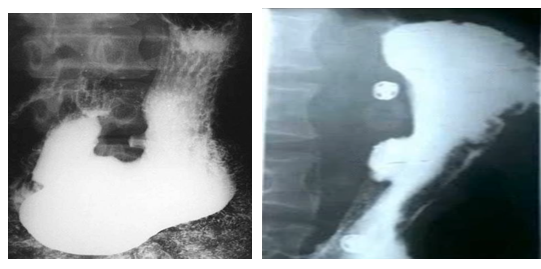

男性,55歲,上腹隱痛約十年,請做出正確診斷

A.胃癌

B.胃潰瘍

C.十二指腸潰瘍

D.食管癌

E.胃憩室

【答案】B